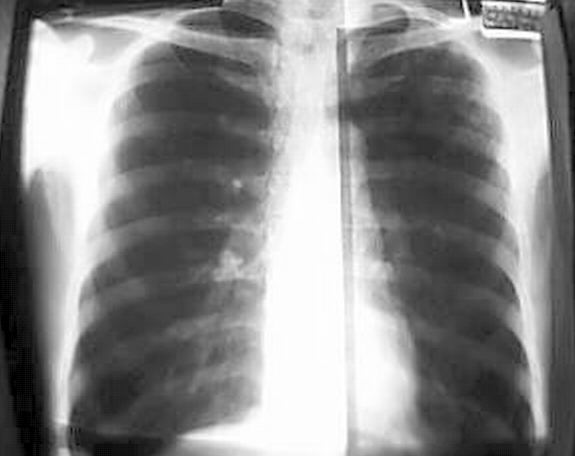

请给看以下问题在那里?

05.05.20片

图像质量不好,就现有后前位胸片看,可疑左上肺胸膜下结节,左三四后肋溶骨性破坏。肺癌肋骨转移?

图像质量不好,就现有后前位胸片看,左三、四、五后肋溶骨性破坏。考虑转移。原发灶待查。[emb7][emb14][emb28][em14]

左三、四、五后肋溶骨性破坏。考虑转移。原发灶待查。